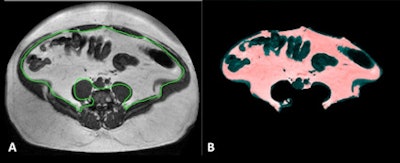

Until now, this has been a very elaborate process. The whole abdomen has to be measured centimeter by centimeter, from the diaphragm to the pelvic floor. The patient has to spend almost 15 minutes in the scanner, and it then takes up to half an hour to analyze an average of 40 sections. But in a study using MRI data from 192 overweight men and women, Schaudinn and his colleagues have found a much quicker way of doing this.

Presenting the study at a scientific session this week at the 96th DRK, he said they started by measuring abdominal fat volumes section by section in the conventional manner, and then compared the results with two much quicker methods in which fat was extrapolated from a single section and from blocks of five sections.

"We can estimate total abdominal fat very accurately from one section," he said. "But if we use blocks of five, the result is even closer to that of a complete analysis."

The team also assessed how the five sections should be chosen to give as accurate a result as possible. In women, they should be taken at the third and fourth lumbar vertebrae, while in men the results are more accurate if a slightly higher measurement is taken at the second and third lumbar vertebrae.